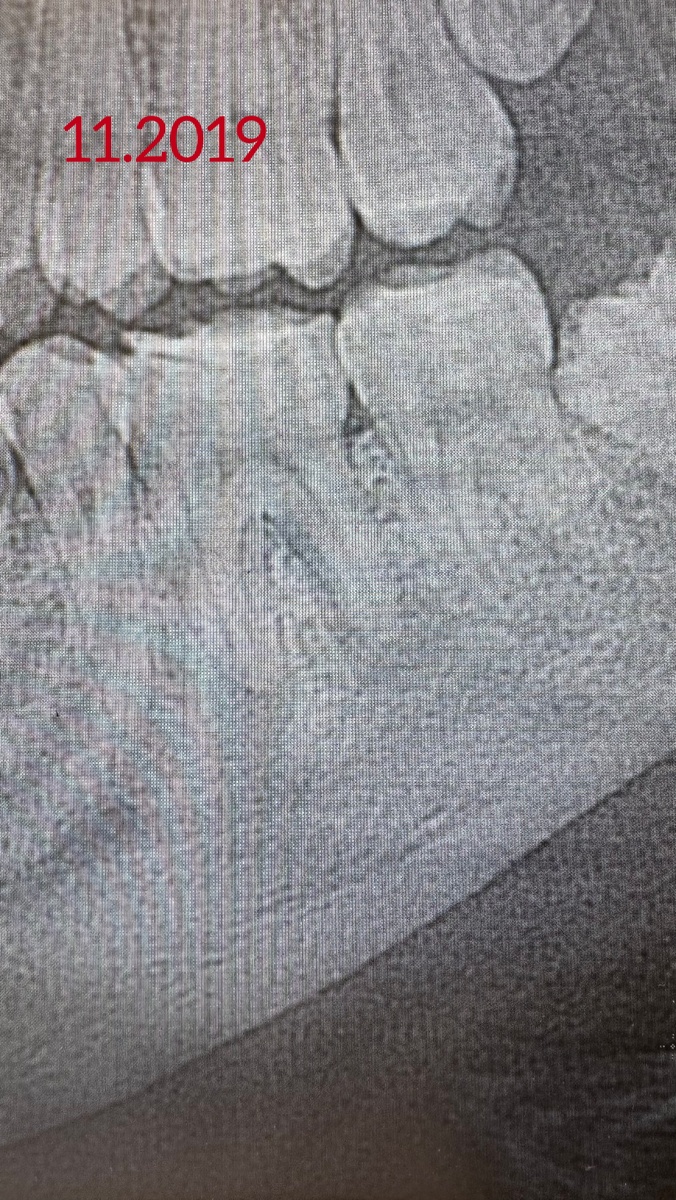

Лечила молодого человека в 2019 году, был свищ на десне возле зуба. Снимки, конечно, не очень хорошего качества, но видно какие были «кисты» на корнях зуба. Специально продублировала снимок и выделила зону воспаления в кости вокруг корня красным цветом.